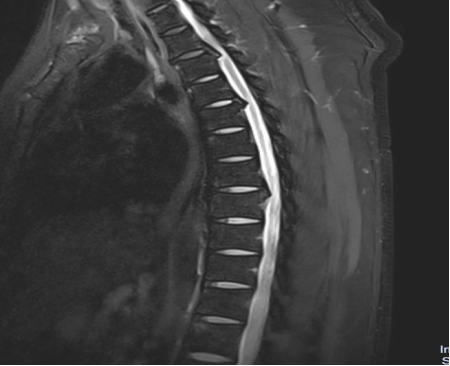

入院后,國(guó)文醫(yī)院骨科迅速組織多名專家會(huì)診,并為吳先生完善了頸椎及胸椎的 MRI 檢查。結(jié)果顯示,吳先生的頸椎及胸椎多階段嚴(yán)重椎管狹窄,脊髓壓迫超過 50%,情況十分危急。經(jīng)過骨科專家團(tuán)隊(duì)的綜合會(huì)診及評(píng)估,最終為他制定了一套個(gè)性化的治療方案,包括頸椎后路單開門椎管減壓頸椎融合內(nèi)固定術(shù),以及胸椎間盤切除伴椎管減壓胸椎植骨融合內(nèi)固定術(shù)。在完善術(shù)前檢查、確認(rèn)無手術(shù)禁忌后,骨科主任呂國(guó)福如期為吳先生實(shí)施了手術(shù)。

手術(shù)涉及頸椎及胸椎多個(gè)階段,操作難度極大。專家團(tuán)隊(duì)采用 “蠶食法” 減壓,分塊去除增生韌帶,最大程度減少對(duì)脊髓的損傷;同時(shí)運(yùn)用椎弓根螺釘固定技術(shù),確保手術(shù)部位的穩(wěn)定性。